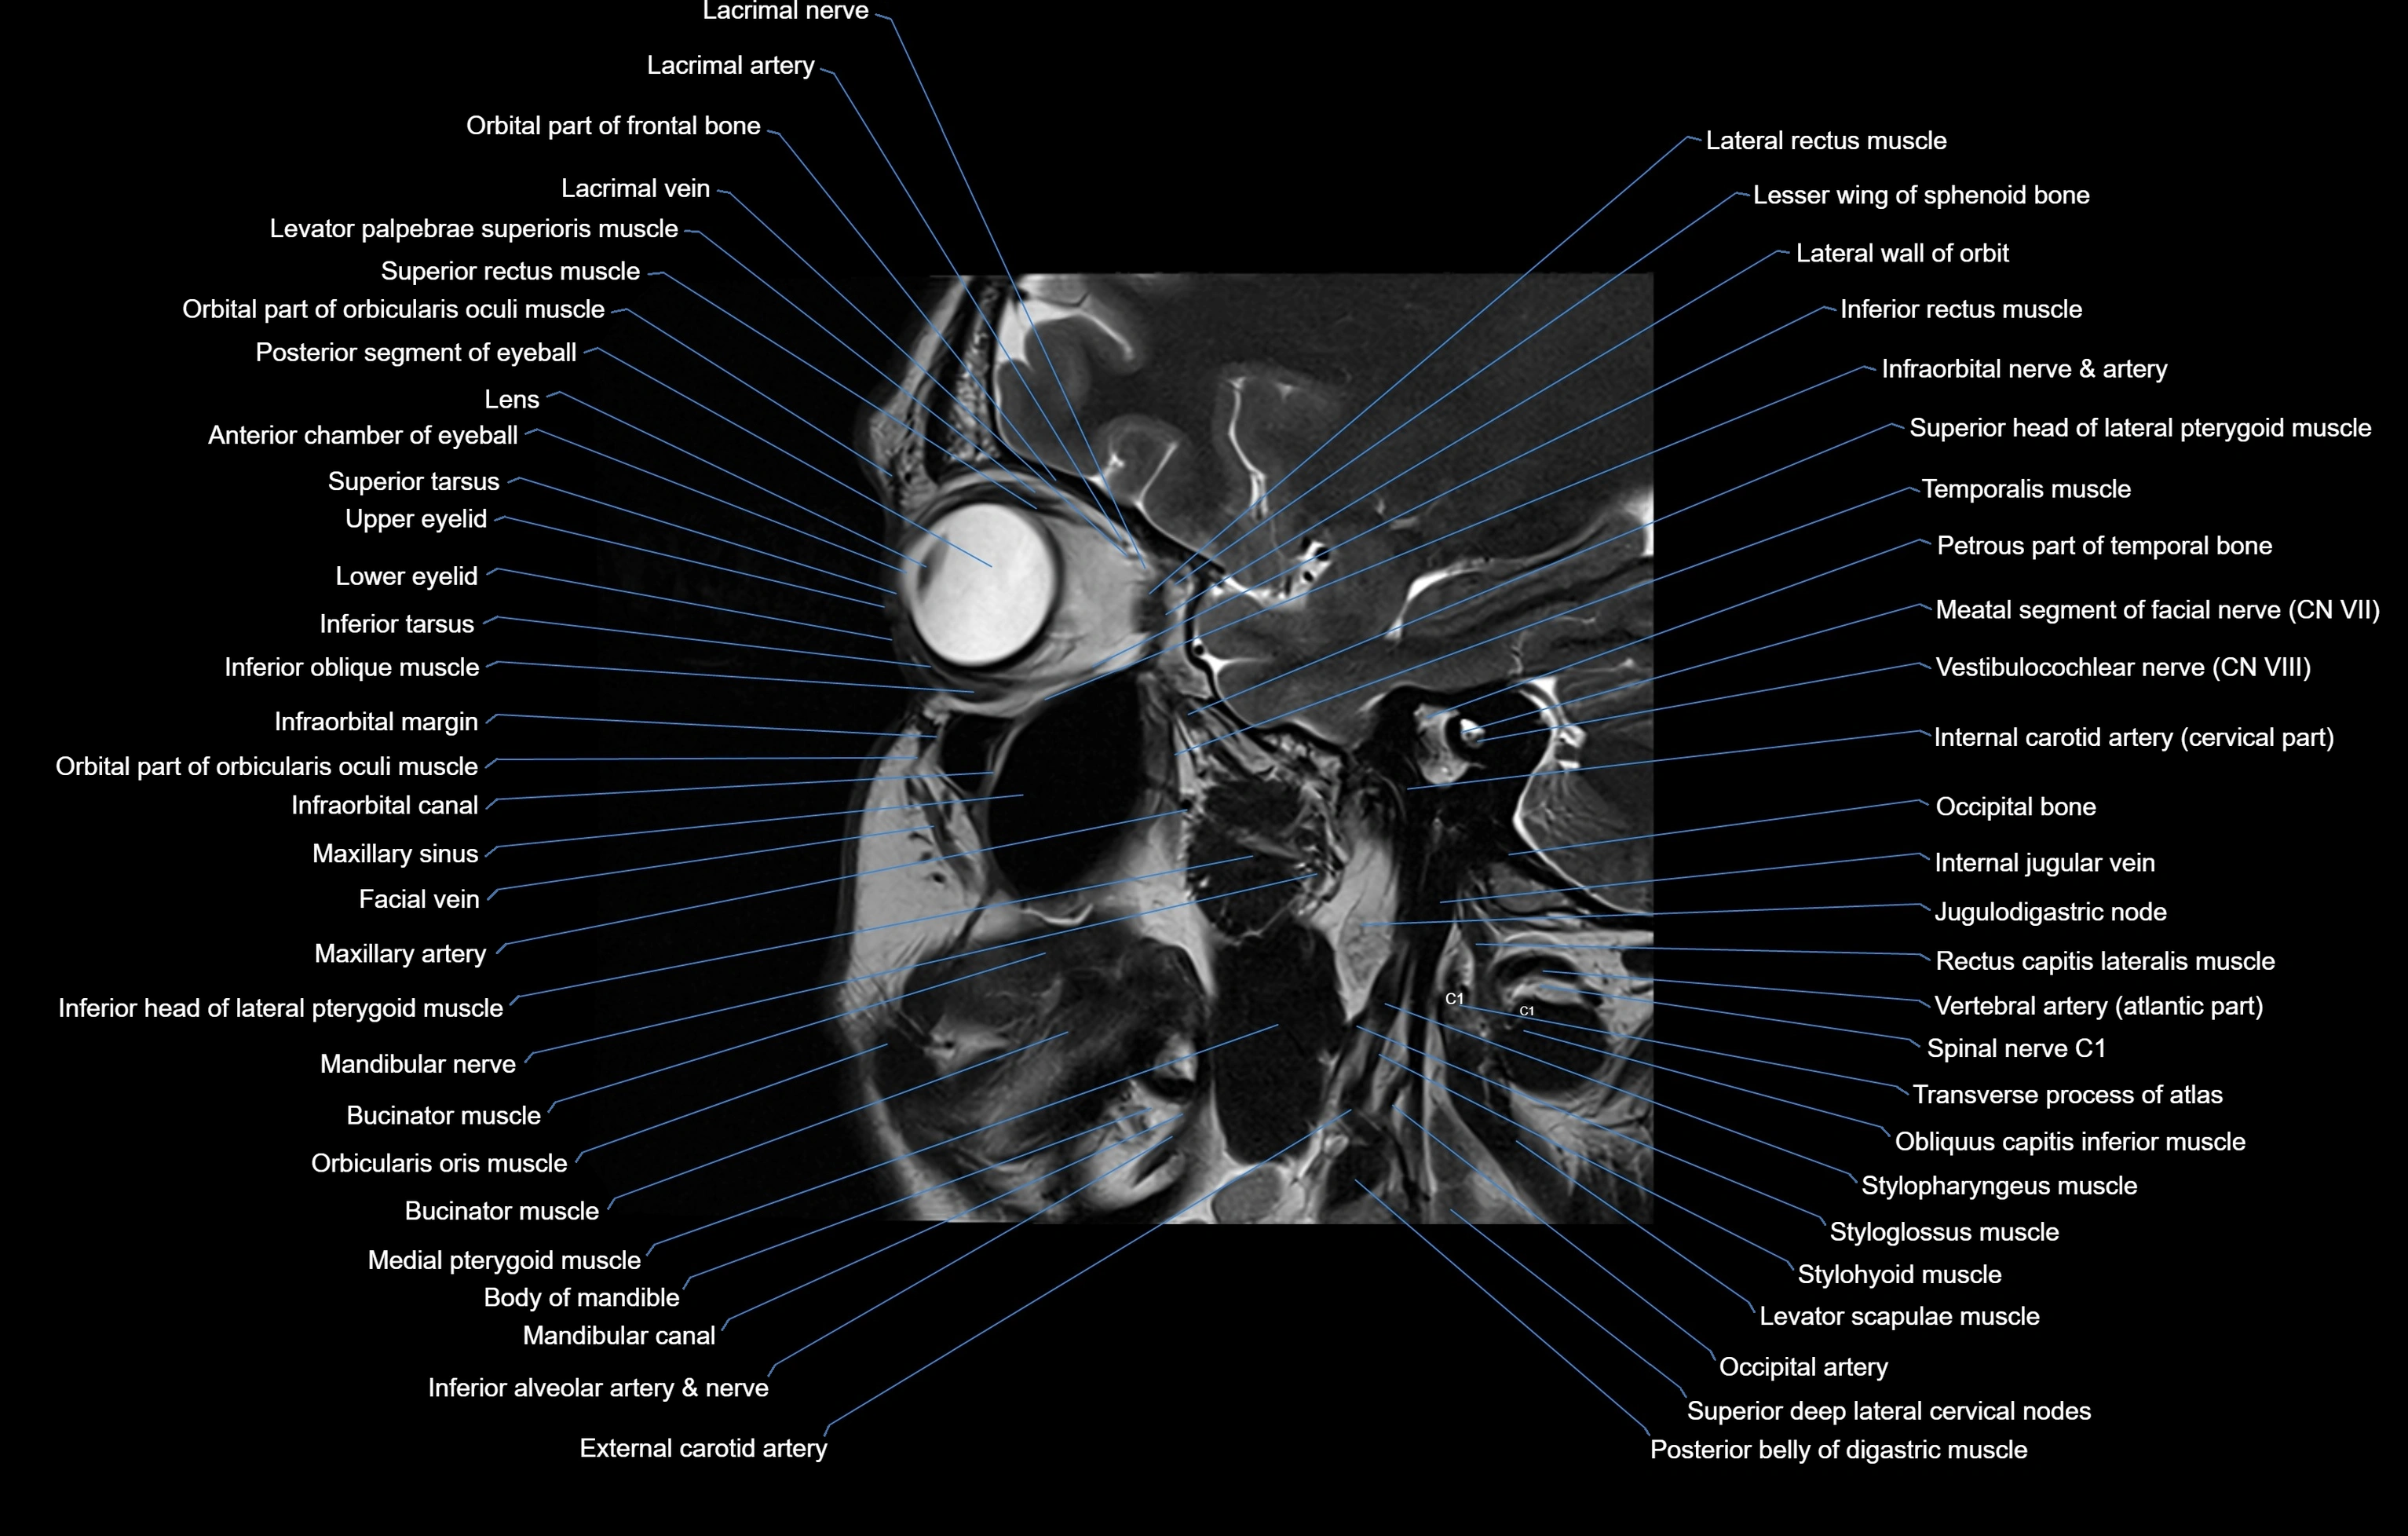

MRI images